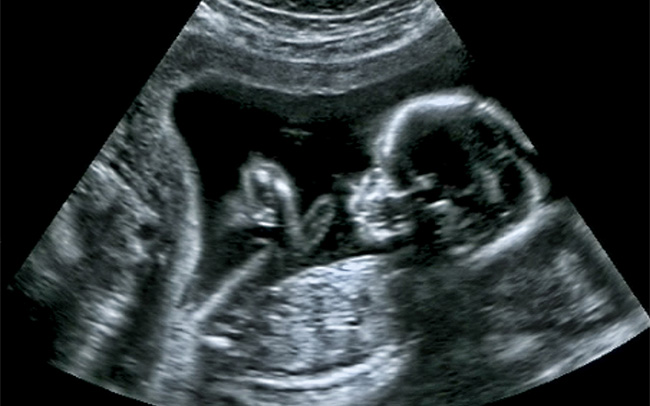

Ultrasound screen close up of baby's head यह याद रखना महत्वपूर्ण है कि स्कैन आपके बच्चे के बारे में और जानने में मदद करने के लिए एक अन्य प्रकार का परिक्षण है। अल्ट्रासाउंड एक चिकित्सा परीक्षा है जिसमें सोनोग्राफर की एकाग्रता की आवश्यकता होती है। इस प्रकार का सुझाव दिया जाता है कि आप अन्य छोटे बच्चे (बच्चों) को घर पर छोड़ दें, जब तक कि यह अनिवार्य न हो। गर्भावस्था में आपको सामान्य रूप से दो स्कैन की पेशकश की जाएगी। पहला स्कैन गर्भावस्था के लगभग 12 सप्ताह में, जिसको डेटिंग स्कैन के रूप में जाना जाता है और दूसरा (कभी-कभी अनामलि स्कैन कहा जाता है) जो लगभग 20 सप्ताह के गर्भ में किया जाता है। यह दूसरा स्कैन आपके बच्चे की हड्डियों, हृदय, मस्तिष्क, रीढ़, चेहरे, गुर्दे और पेट की विस्तार से जांच करेगा। यह याद रखना महत्वपूर्ण है कि स्कैन में सभी कुछ नहीं पाया जा सकता जो आपके बच्चे के लिए चिंता का विषय हो सकता है। इमेजिस की गुणवत्ता बॉडी मास इंडेक्स और फाइब्रॉएड सहित कई कारकों पर निर्भर करती है। यदि आप अपने बच्चे का लिंग जानना चाहती हैं, तो आप सोनोग्राफर से पूछ सकती हैं, हालाँकि यह हमेशा स्पष्ट रूप से देखना संभव नहीं होता है। UK में सभी गर्भवती महिलाओं को प्रसवपूर्व जांच की पेशकश की जाती है। गर्भावस्था में एक स्क्रीनिंग टेस्ट आपको इस बारे कि आपके बच्चे को कोई बीमारी है या नहीं, का हाँ/ना में जवाब नहीं दे सकता है । केवल आपको यह बता सकता है कि आपके बच्चे के प्रभावित होने की कितनी संभावनाएं हैं। गर्भावस्था में स्क्रीनिंग परिक्षणों में रक्त परिक्षण और अल्ट्रासाउंड स्कैन शामिल हैं (अल्ट्रासाउंड स्कैन सुझाव दे सकते हैं कि कोई बीमारी हो सकती है (जैसे डाउन सिंड्रोम के लिए स्क्रीनिंग में) या पुष्टि करेगा कि कोई बीमारी है (जैसे स्पाइना बिफिडा का पता लगाने में))।